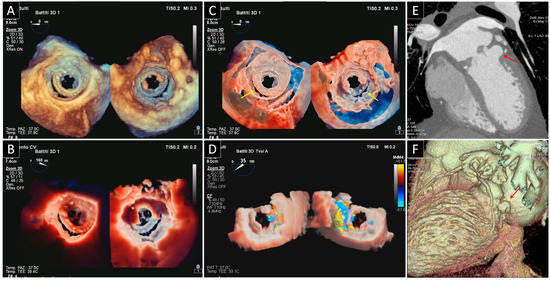

3. Prosthetic Paravalvular Leak

3.1. Mitral Paravalvular Leak

3.2. Aortic Paravalvular Leak